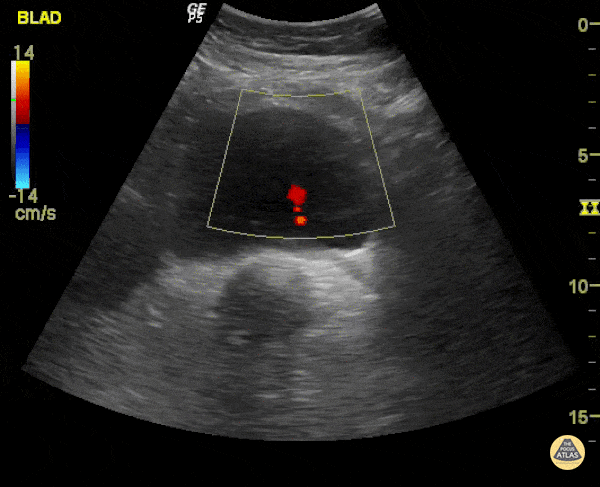

Renal/GU - Ureteric Jet

When an obstructing stone is suspected, measurement of the ureteric jets can be performed to see if the ureters are draining into the bladder. In this study, there is no left ureteric jet demonstrating obstruction of the right ureter, and likely an obstructing stone. Renal US is likely to demonstrate hydronephrosis of the right kidney. Dr. Justin Bowra et al.